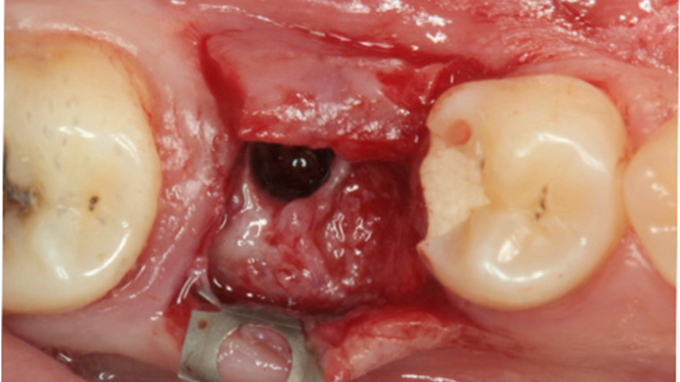

Clinical case: # 46 implant placement & GBR using i-Gen membrane for significant vertical resorption & mixed bone defect

- Courtesy of Dr. Iulian Filipov, Romania -

AnyRidge, mandibular posterior, i-Gen, resorption, bone defect, bone regeneration, space management, #46, GBR, Dr. Iulian Filipov